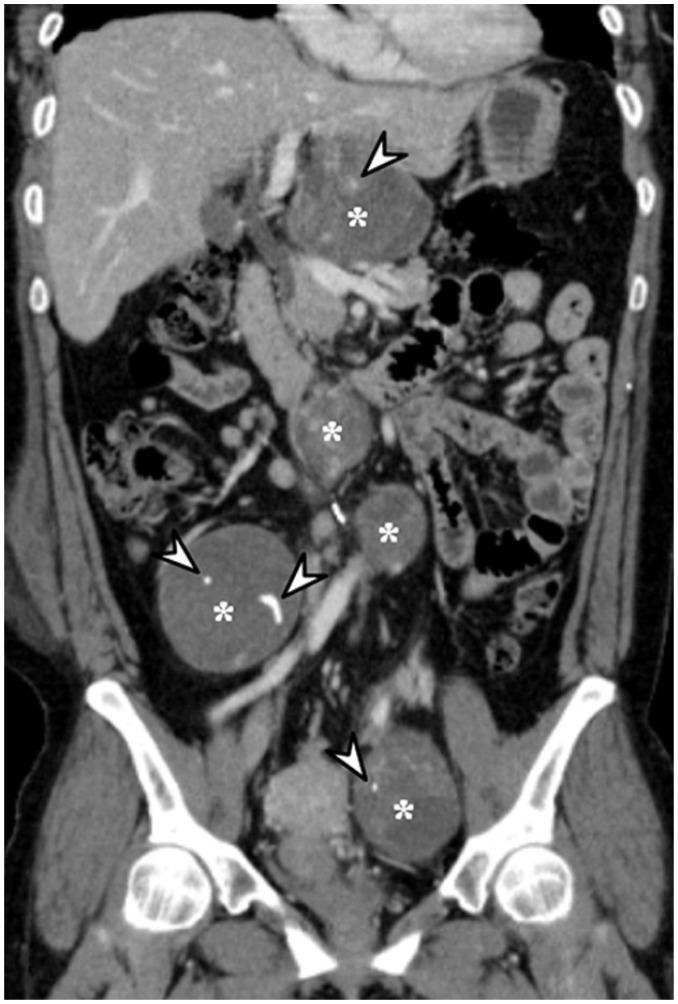

腹盆腔内肿瘤内钙化的影像学表现

Imaging Patterns of Intratumoral Calcification in the Abdominopelvic Cavity.

Intratumoral calcification is one of the most noticeable of radiologic findings. It facilitates detection and provides information important for correctly diagnosing tumors. In the abdominopelvic cavity, a wide variety of tumors have calcifications with various imaging features, though the majority of such calcifications are dystrophic in nature. In this article, we classify the imaging patterns of intratumoral calcification according to number, location, and morphology. Then, we describe commonly-encountered abdominopelvic tumors containing typical calcification patterns, focusing on their differentiable characteristics using the imaging patterns of intratumoral calcification.

摘要

肿瘤内钙化是最显著的放射学表现之一。它有助于肿瘤的检测,并为正确诊断肿瘤提供重要信息。在腹盆腔内,多种肿瘤会出现具有不同影像特征的钙化,不过此类钙化大多属于营养不良性钙化。在本文中,我们根据数量、位置和形态对肿瘤内钙化的影像模式进行分类。然后,我们描述含有典型钙化模式的常见腹盆腔肿瘤,重点介绍利用肿瘤内钙化的影像模式进行鉴别诊断的特征。